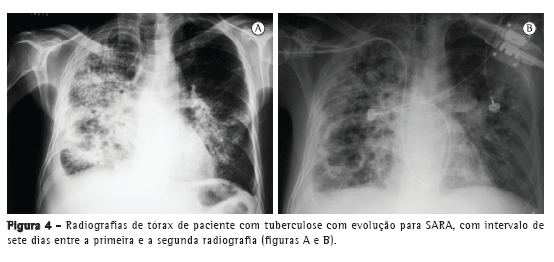

Com relação aos achados radiológicos, infiltrados reticulares e consolidação são os padrões mais frequentes,(5,6,10,15,17) sendo que cavitação pode estar presente em 27-50% dos casos.(6,10,16) As Figuras 1 a 4 mostram alguns dos principais padrões radiológicos nesse contexto.

A principal causa de internação em UTI foi a insuficiência respiratória, e o escore Acute Physiology and Chronic Health Evaluation II (APACHE II) variou de 13 a 23 na maioria dos estudos.(5,6,10,15,17) Alguns autores avaliaram os fatores associados ao desenvolvimento de insuficiência respiratória e necessidade de VM. Pneumonia ou sepse por germes gram-negativos, DPOC, história de tratamento irregular para tuberculose e neoplasia foram fatores preditores de insuficiência respiratória.(9) Em uma série de 13 casos, 7 e 6 pacientes, respectivamente, apresentavam tuberculose miliar/disseminada e pneumonia tuberculosa, necessitando cuidados intensivos. Comparados com os pacientes com pneumonia tuberculosa, os pacientes com tuberculose miliar/disseminada foram mais propensos a necessitar VM (18,9% vs. 0,8%; p < 0,0001).(8)

O tempo entre o início dos sintomas e o início do tratamento antituberculose descrito nos estudos foi maior do que 30 dias em 28,8-34,0% dos casos.(6,17) O tempo entre a admissão e o início da terapêutica adequada foi avaliado em apenas um estudo, sendo relatada uma média de 4,3 dias. Naquele estudo retrospectivo, o tempo entre a admissão e o início do tratamento foi menor nos pacientes com tuberculose miliar do que naqueles com pneumonia tuberculosa (2,8 ± 2,5 dias vs. 5,0 ± 7,0 dias; p = 0,048).(16) Pode haver atraso no diagnóstico e, consequentemente, no começo do tratamento pela difícil diferenciação radiológica entre pneumonia tuberculosa e pneumonia bacteriana grave. Considerando essa dificuldade na distinção entre as duas patologias, um estudo avaliou as diferenças nas características clínicas e radiológicas de pacientes com pneumonia grave com e sem tuberculose internados em UTIs. A história de sintomas com duração maior do que duas semanas e a presença de micronódulos ou de padrão cavitário na radiografia de tórax foram significativamente associados com tuberculose pulmonar ativa.(20) Adicionalmente, o padrão miliar na radiografia de tórax também pode ser erroneamente interpretado como insuficiência cardíaca congestiva.(18)

Pelo exposto acima, o papel da radiografia de tórax no diagnóstico clínico da tuberculose pulmonar permanece incerto em pacientes em UTIs, podendo não contribuir tanto quanto o esperado. Em um estudo caso-controle, 89 pacientes com tuberculose pulmonar e um número igual de controles foram avaliados, sendo que o padrão radiológico mais comumente encontrado foi a consolidação, em 61 pacientes (6,5%). Na análise multivariada, a história de tuberculose pulmonar prévia foi associada com a suspeita clínica de tuberculose, mas os padrões radiológicos não foram associados a essa suspeita.(21)